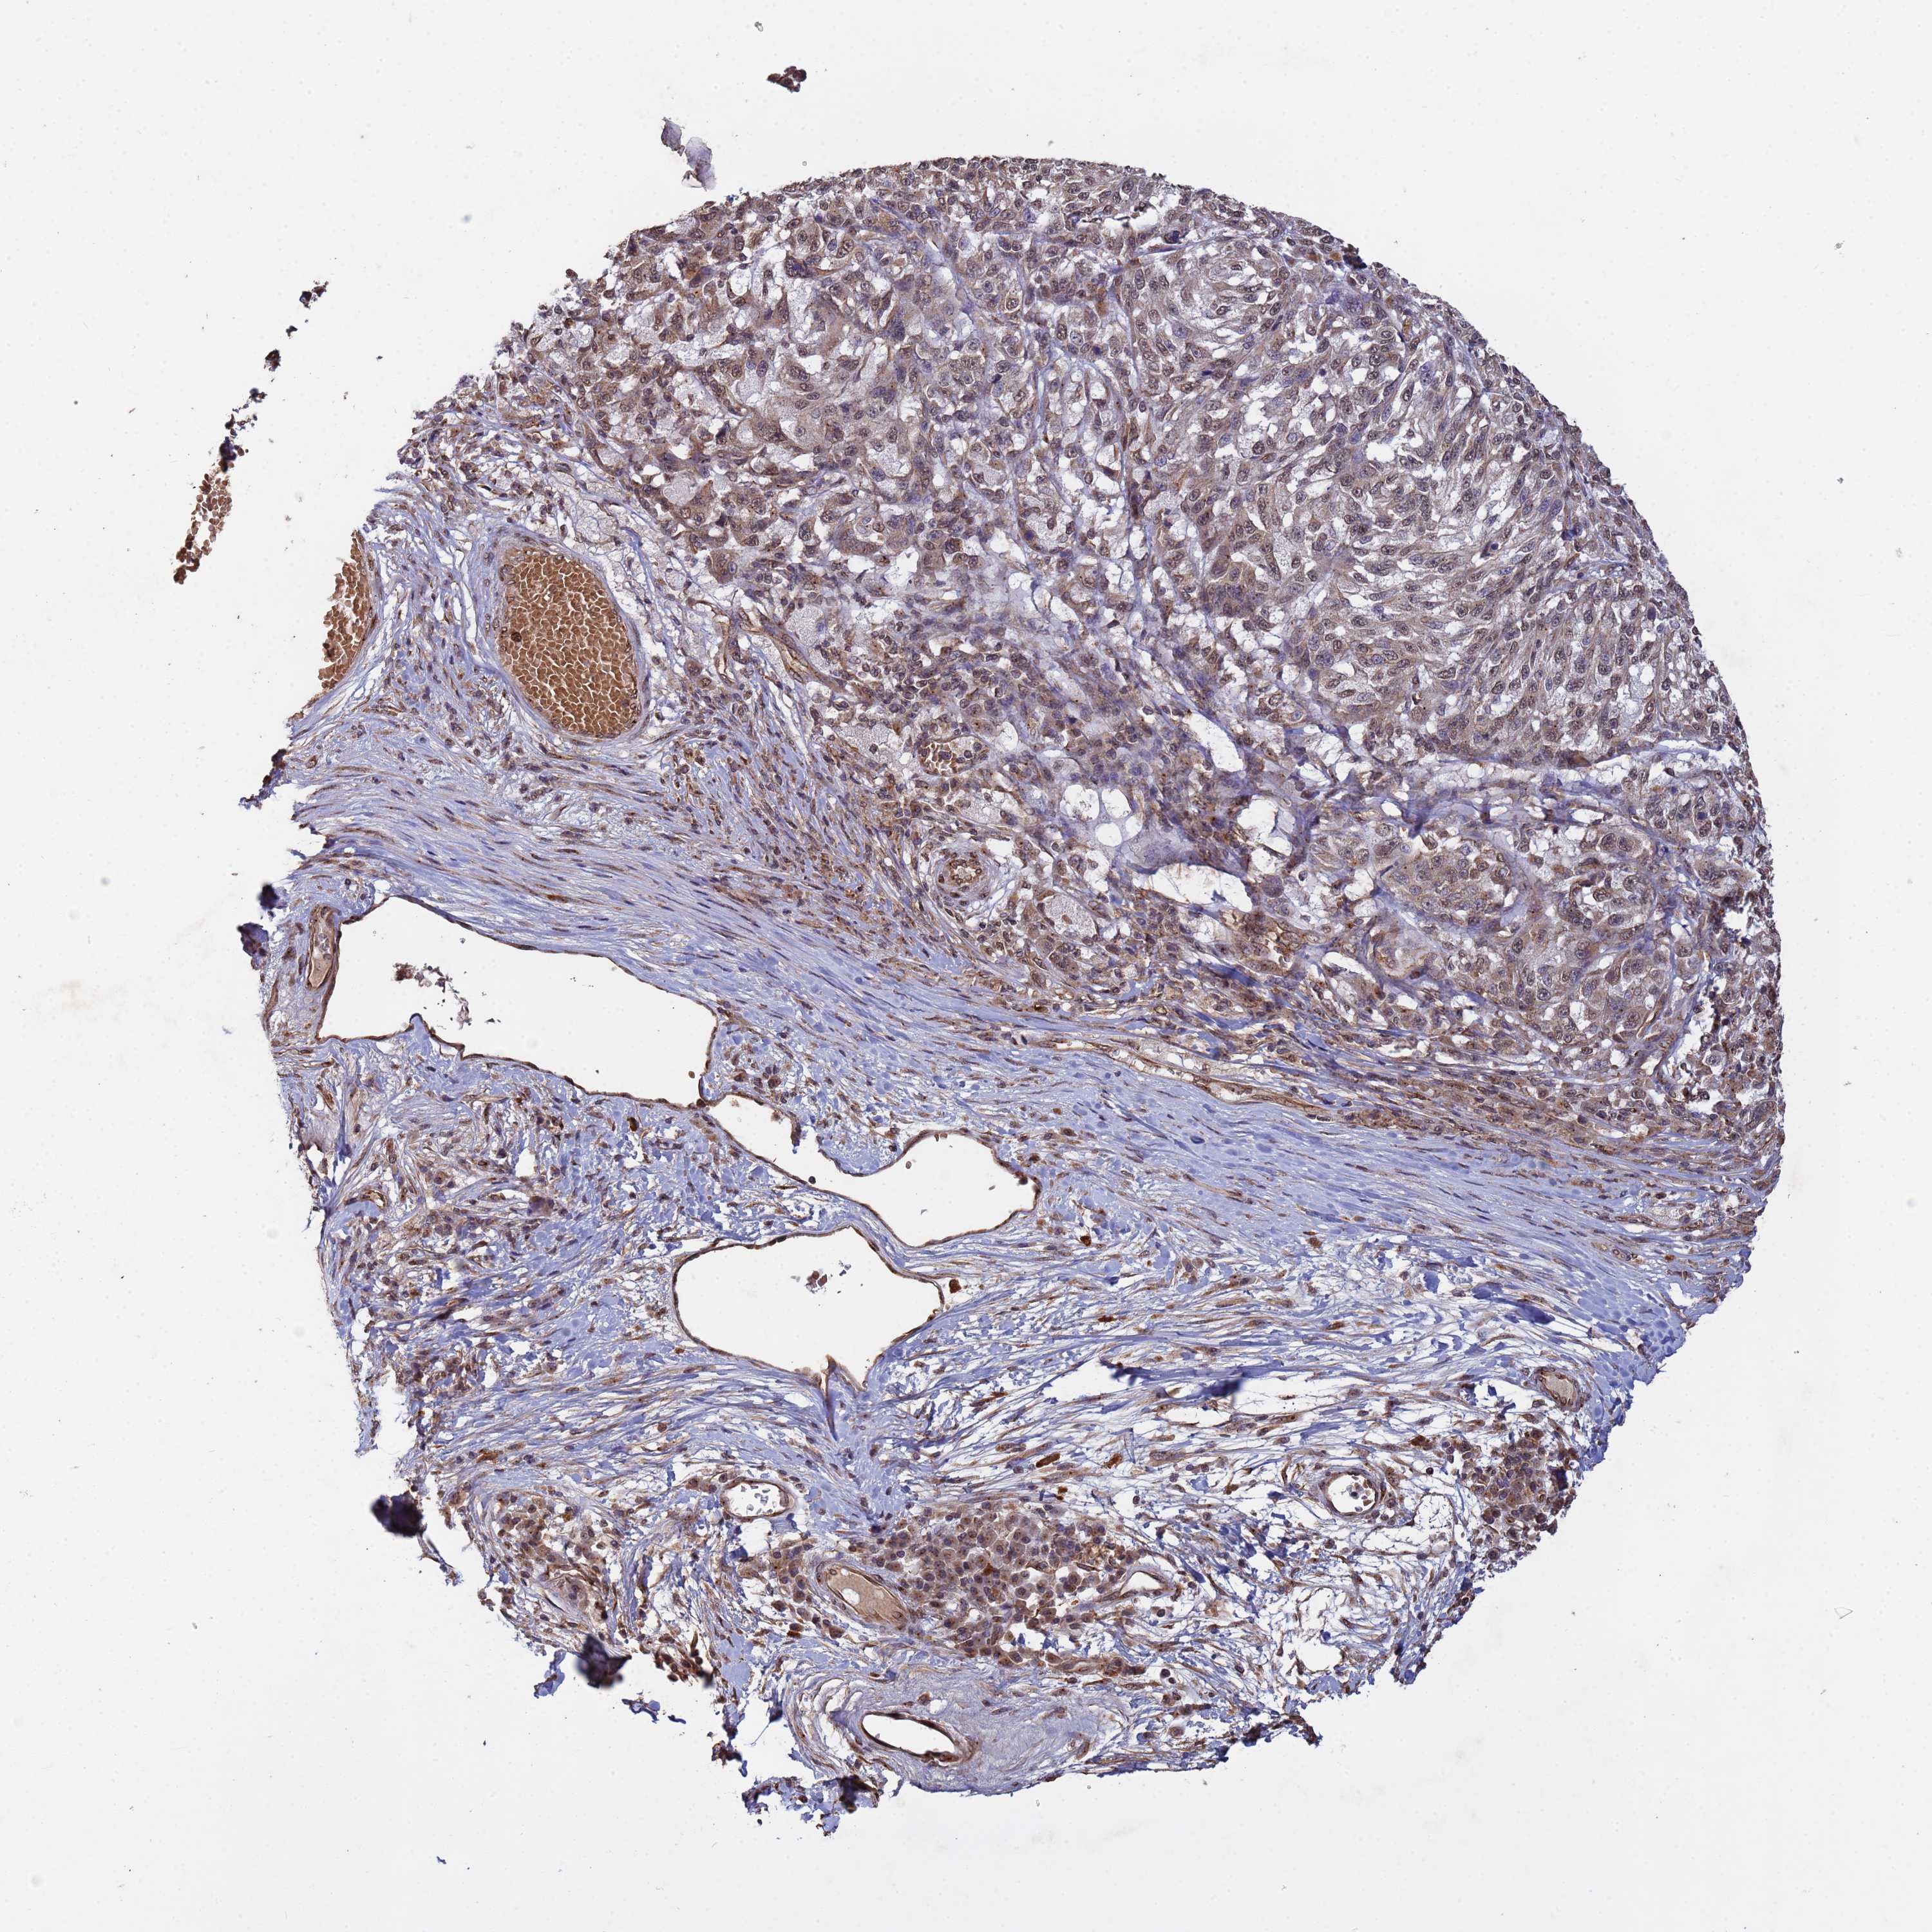

MELANOMA - Protein expressioni

A mouse-over function shows sample information and annotation data. Click on an image to view it in a full screen mode. Samples can be filtered based on level of antibody staining by selecting one or several of the following categories: high, medium, low and not detected. The assay and annotation is described here.

Note that samples used for immunohistochemistry by the Human Protein Atlas do not correspond to samples in the TCGA dataset.

Antibody stainingi

Antibody staining in the annotated cell types in the current human tissue is reported as not detected, low, medium, or high, based on conventional immunohistochemistry profiling in selected tissues. This score is based on the combination of the staining intensity and fraction of stained cells.

Each image is clickable and will lead to virtual microscopy that enables deeper exploration of all samples and also displays staining intensity scores, fraction scores and subcellular localization as well as patient and tissue information for each sample.

Antibody HPA045624

Staining

High

Medium

Low

Not detected

Intensity

Strong

Moderate

Weak

Negative

Quantity

>75%

75%-25%

<25%

None

Location

Nuclear

Cytoplasmic/membranous

Cytoplasmic/membranous,nuclear

Malignant melanoma, NOS

Malignant melanoma, Metastatic site